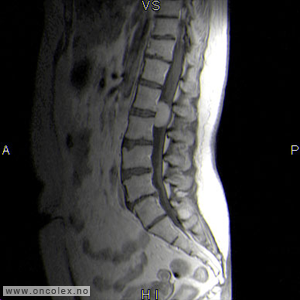

Bildediagnostiske undersøkelser

MR er det viktigste diagnostiske hjelpemiddel for å påvise svulst i ryggmargen, ryggmargsnervene og ryggmargshinnene. CT kan også brukes, men har klare begrensninger når det gjelder fremstilling av svulstene. Blant annet kan svulster som ikke tar opp kontrast bli oversett. CT og skjelettrøntgen kan imidlertid være nyttig for å kartlegge grad av skjelettødeleggelse og eventuell instabilitet i ryggsøylen.